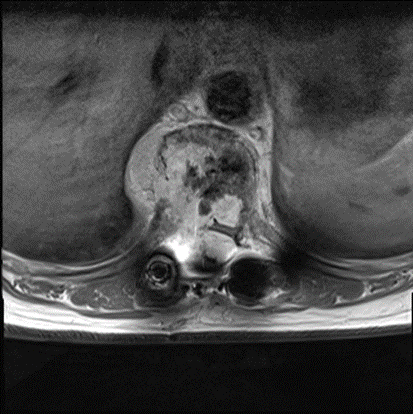

王晋团队首先精准寻找并结扎肿瘤的滋养血管 , 显著减少肿瘤的血管 , 再应用超声骨刀技术和双极精准止血技术 , 进一步减少出血 , 在实时监控脊髓功能条件下 , 成功切除肿瘤 , 实现了三节段胸椎整块切除 , 手术耗时4个小时 , 术中出血仅为1800ml 。

拆除压迫神经的肿块后 , 她恢复行走能力

令人欣慰的是 , 卜女士术后生命体征平稳 , 术后仅仅在ICU观察了1天便转回普通病房 。 术后病理结果显示 , 卜女士的脊柱肿瘤为梭形细胞血管瘤 , 属于良性肿瘤 。 经过16天的住院康复护理 , 卜女士的下肢肌力达到3级 , 可以出院啦!